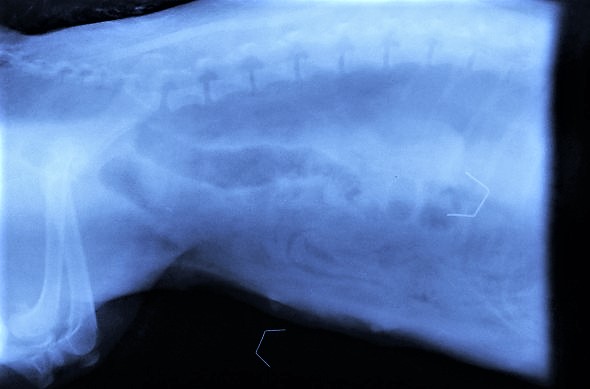

To be perfectly honest though, we ended up riping apart one of the clinic's sofas to get one of these staples and xray it by the side of Hara's belly, only to confirm that the one inside her stomach was of the same shape and size as the staple that holds the covers of the sofa together!!!

The good thing in Hara´s case was that a staple, as all metallic objects, is easily identified on an xray. Other foreign bodies that dogs very often swallow (socks, plastic objects, linear etc), are very difficult to identify and in most cases they are not visible on xrays.

The size and type of this foreign body would not allow any delays. We decided to operate on Hara and remove the foreign object by performing a gastrotomy (opening into her stomach). Finding the staple inside Hara's stomach was a true challenge as it was covered in hair (due to overgrooming!), but that was a good thing, as the hair did not allow the sharp ends of the staple to penetrate the wall of the stomach.